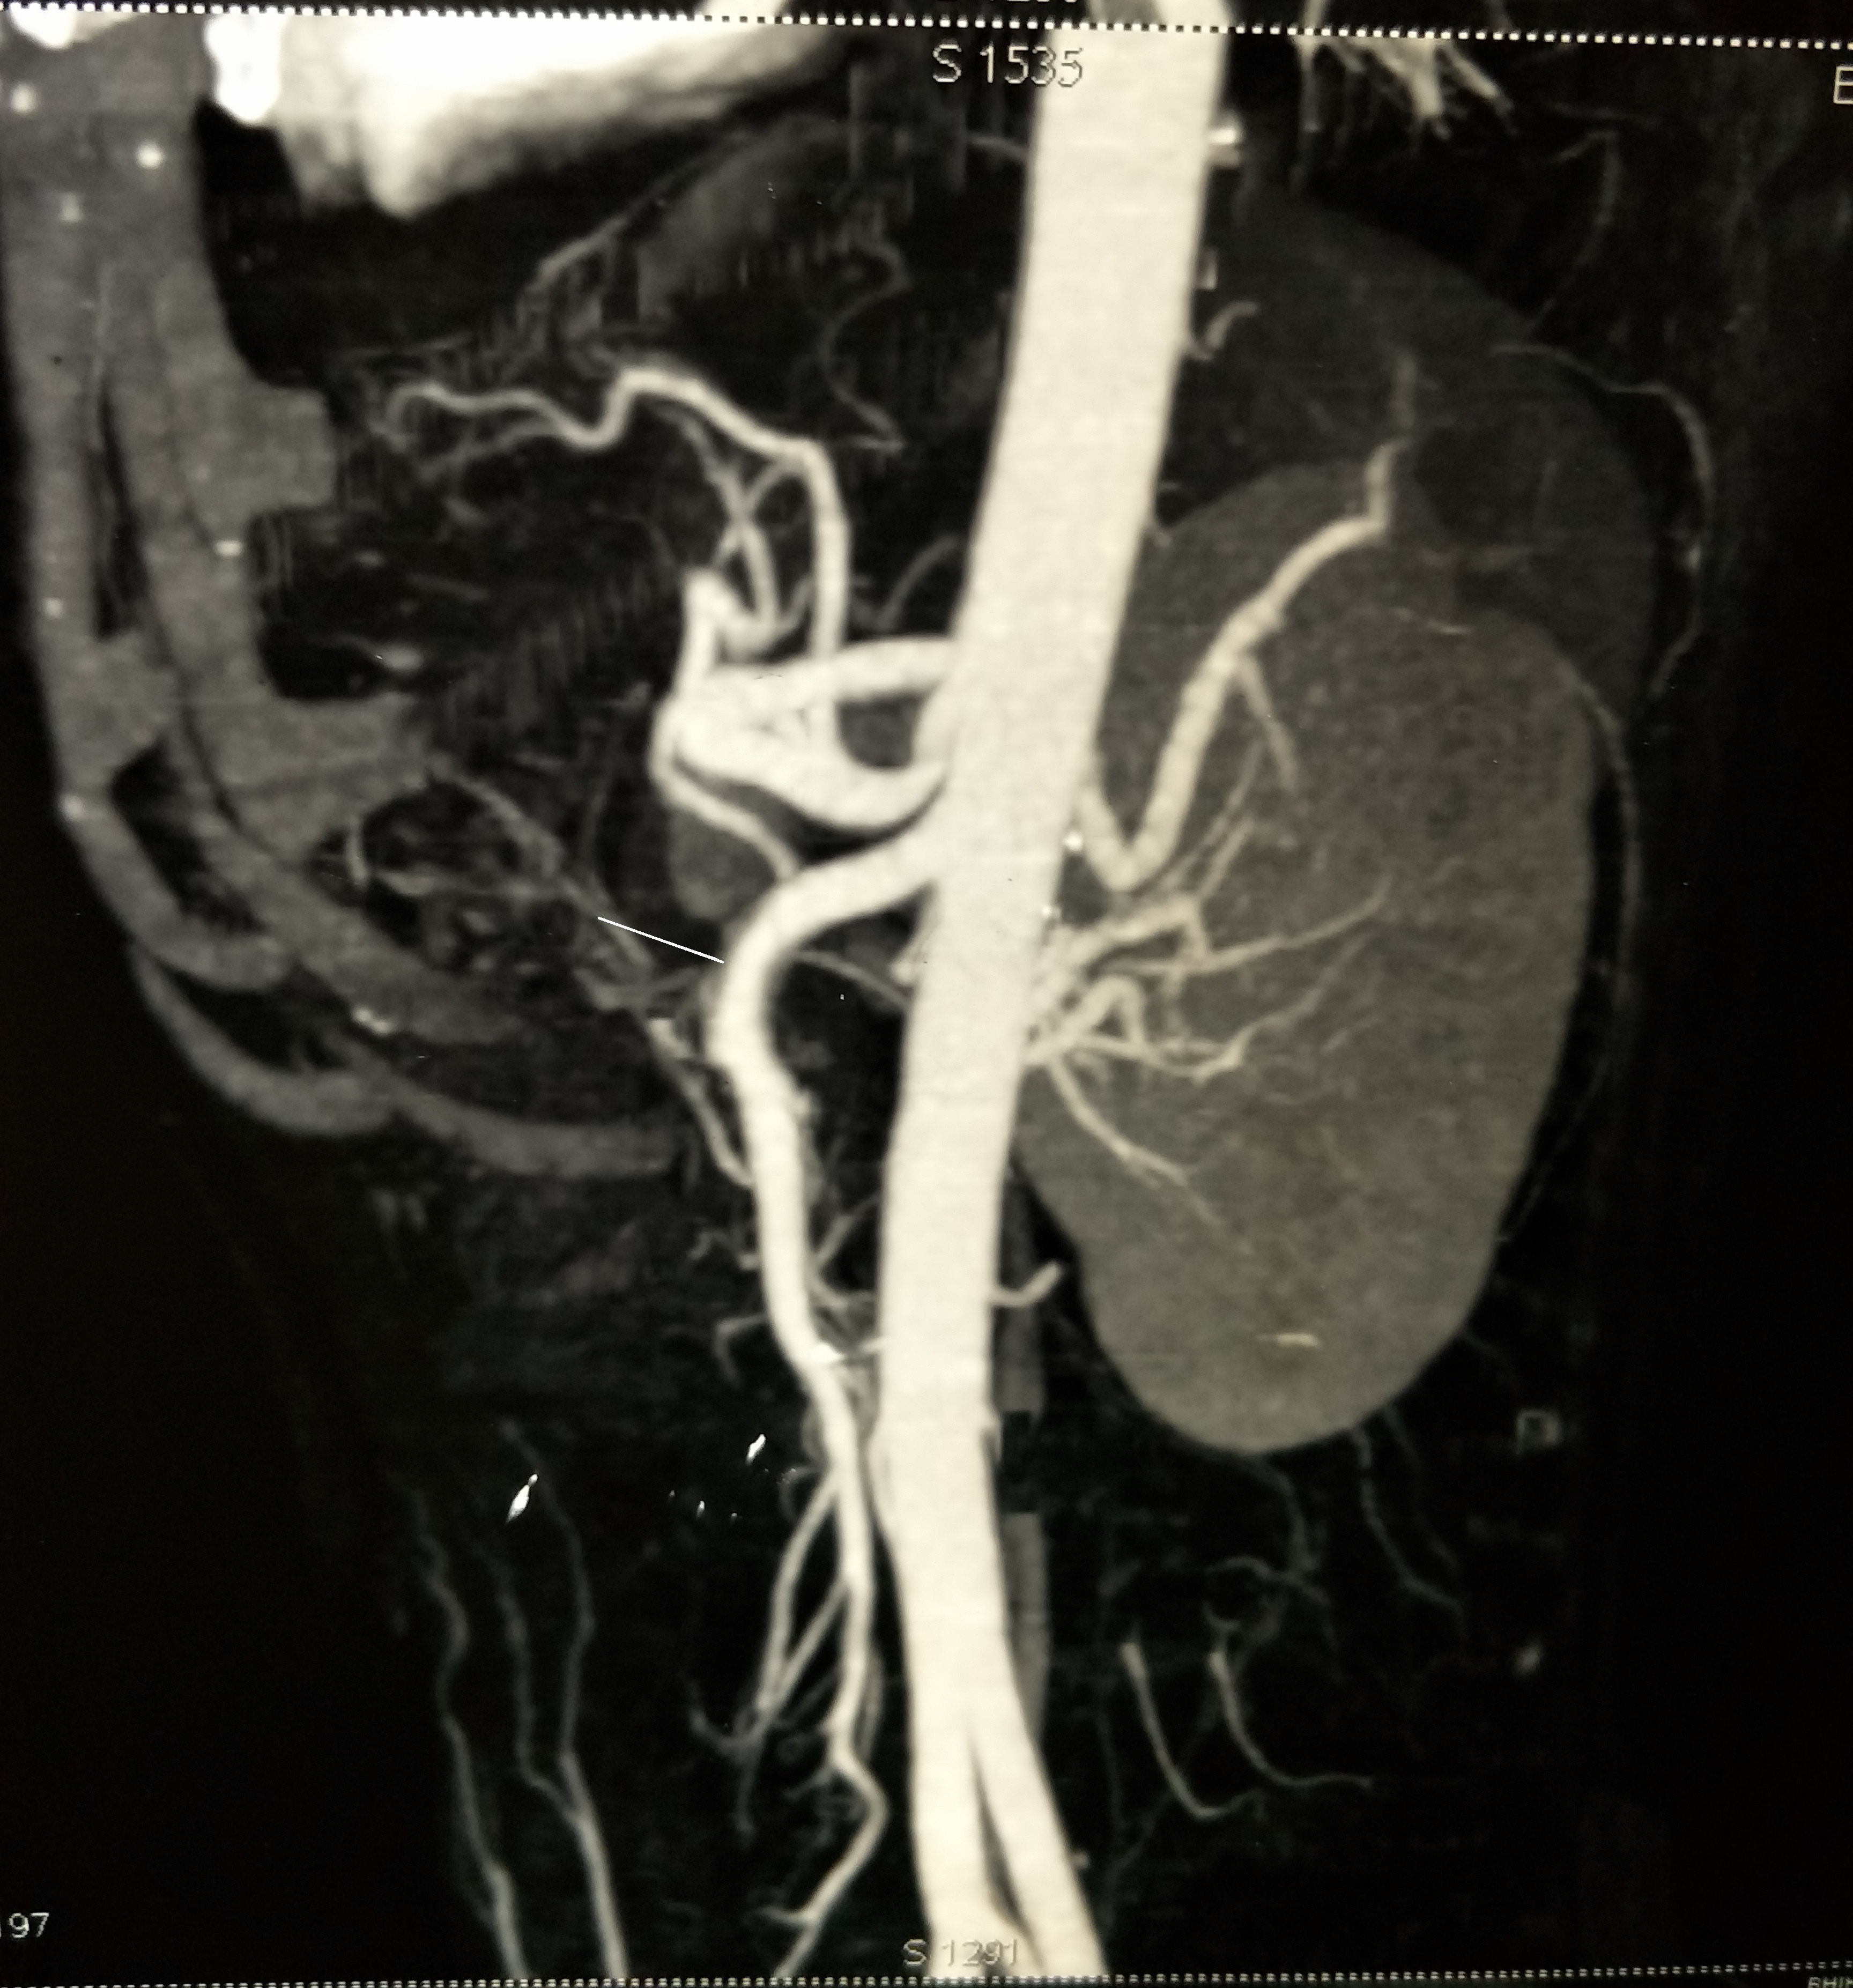

A 30-year-old male patient presented with abdominal pain and vomiting for three days. He was known to be diabetic and presented to the surgical outpatients’ department with the complaint of abdominal pain, on and off for three months. He did not smoke or drink alcohol. There was no history of hematemesis or melena. On physical examination, the temperature was normal, pulse 110/min, respiratory rate 18/min, and blood pressure 140/86 mmHg. Minimal epigastric tenderness was elicited on palpation and bowel sounds were auscultated. Rectal examination was normal. Laboratory findings were normal with a hemoglobin of 14.3g/dL, hematocrit 42%, platelets 425,000/mm3, and white blood cell count 10,000/mm3. Serum analysis revealed the following: random blood sugar, 332mg/dL; aspartate aminotransferase, 24U/L; alanine aminotransferase, 22U/L; and creatinine, 1.0mg/dL. Coagulation profile including PT with INR and aPTT were normal. An ultrasound of the abdomen revealed normal findings. We performed a contrast-enhanced computed tomography scan, which showed a small contrast-filled pouch in the proximal superior mesenteric artery (SMA) (Figure 1,2). However, all other branches showed normal vascularity and the SMA origin was normal. No thrombus was seen within the lumen of the vessel. 3D reconstruction imaging revealed mild enlargement of the SMA with a contrast-filled pouch (Figure 3). We treated the patient conservatively using low molecular weight heparin and tablet aspirin 150 mg daily for anticoagulation. The patient improved and was discharged on warfarin. He was in followed up for six weeks without any problems, and then was lost to follow-up.

Figure 3 3D reconstruction demonstrates an enlarged superior mesenteric artery lumen with contrast filled pouch.